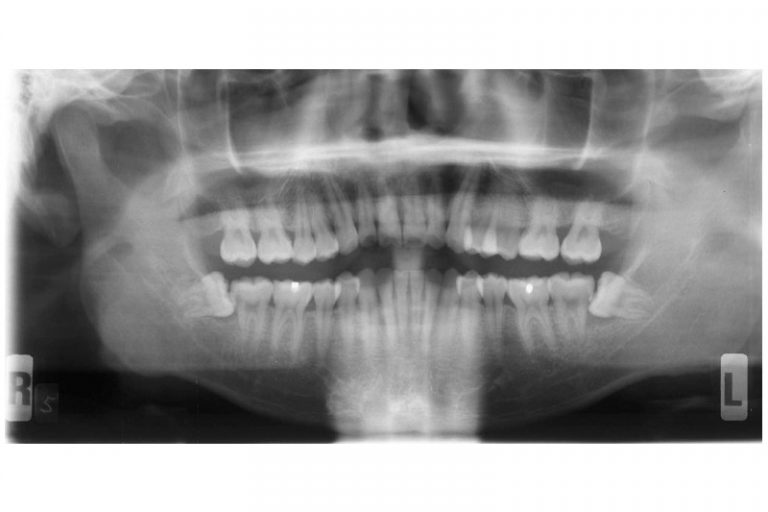

全口X光片顯示 下顎左右有阻生智慧齒

即使沒有症狀,也有隱藏問題,所以應該定期找牙醫檢查,若出現隱藏的問題,就算不痛亦應拔除智慧齒。阻生等可能會導致牙周病或蛀牙, ,令旁邊本來有用的大牙或其牙骨缺損,但當患者開始疼痛的時候才處理已經太遲。因此建議在18至20歲左右前往牙醫診所檢查並拍攝一張X光片,判斷是否有阻生並需要剝牙。大部份人的智慧齒也沒有足夠位置長出,在有限的空間下成長會導致阻生,無論它生長的角度如何都可能導致上述口腔的問題。